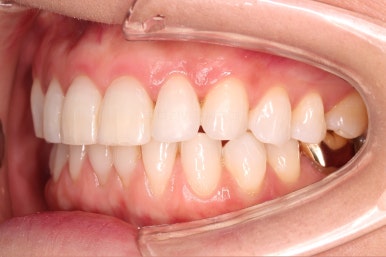

환자분이 원하시는 만큼 가지런해졌고, 부가적으로 생길 수 있는 부분들도 수용 가능한 선에서 잘 마무리가 되었습니다.

3개월이라는 빠른 기간 내에(심미보철 보다 약간만 더 긴 시간) 치아의 손상없이 마무리를 잘 했습니다.

아래 앞니는 부분교정까지는 원하지 않으셔서 약간 다듬어 드리고 종료했습니다.

이상 부분교정과 앞니 심미보철을 고민하셨던 분을 연산동부분교정 잘 개선했던 치료사례였습니다.